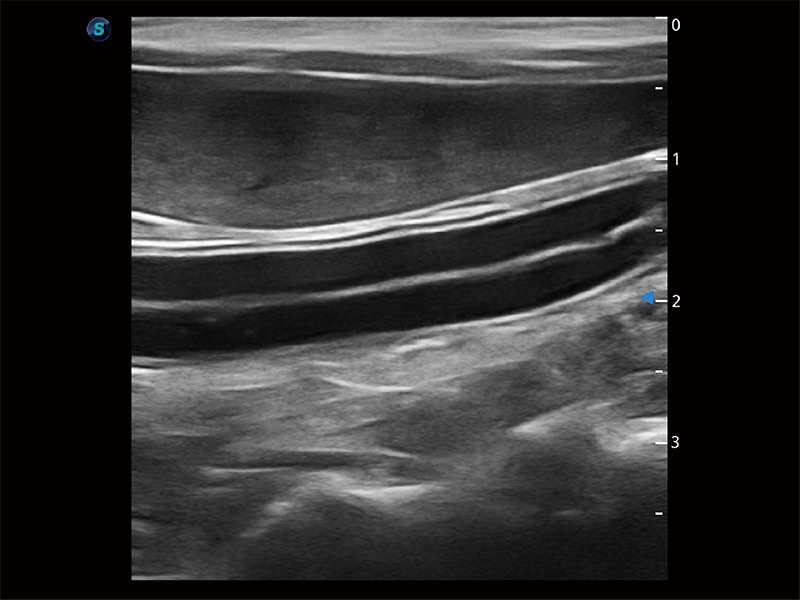

操作簡便,無需高頻度外力作用即可真實(shí)反映組織的形變,快速評估腫瘤良惡性。